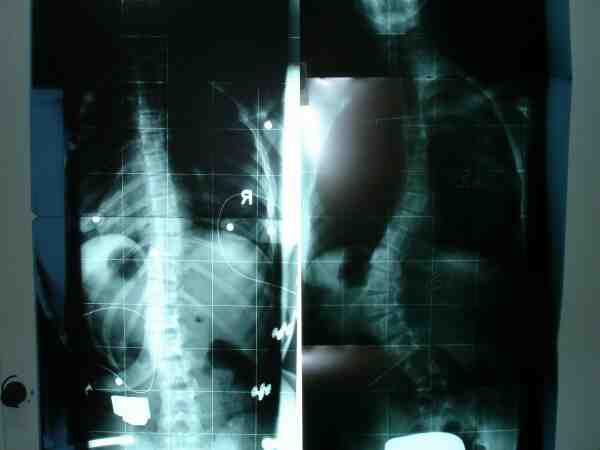

Sorry sollte nicht so sein.

hier das Bild von Iris

Iris21.jpg

Iris21.jpg (10.04 KiB) 14490 mal betrachtet